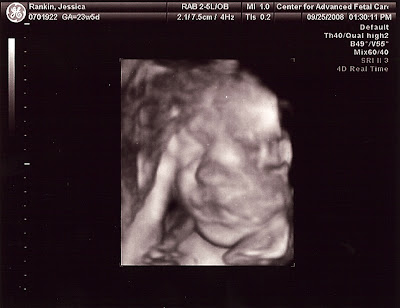

Well, we hit the 23 week mark with Baby Rankin. We went in this morning for our sonogram that showed us that we have a healthy baby growing exactly to the date! It was very exciting for all of us to see, we especially felt blessed when we watched the baby yawn. Technology is so amazing! All the vitals and development looked wonderful. Praise be to God! Ainsley is excited and anxiously awaiting when the baby will arrive.

We also would like to ask for your prayers though at this time. During the sonogram, they discovered that I have placenta previa. I've switched to a high-risk doctor and have had an appointment with him. He is a wonderful doctor and very reassuring. We'll be monitoring the situation every 4-6 weeks to see if the placenta migrates away from what Matthew refers to as "the exit hatch." If not, I'm looking at a C-section for this baby. We ask that everyone would pray that both mom and baby stay healthy, that we would be able to deliver naturally, and that the doctors would have wisdom in our management plan. Thank you in advance for your prayers, we'll keep you posted.